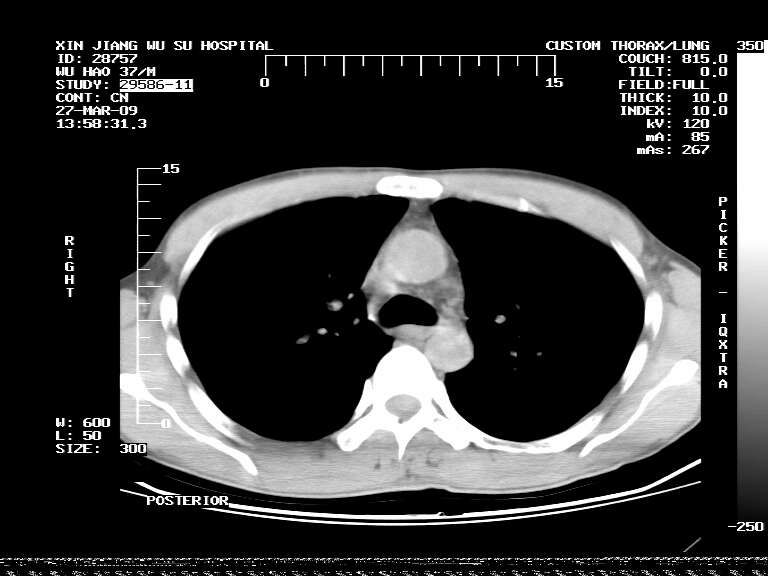

男,37岁,体检胸透发现阴影。

患者体检发现 无症状 左肺下叶占位,边缘模糊,可见血管聚束、分叶、胸膜牵拉,增强呈不均匀性强化。 首先考虑左肺下叶周围型肺癌,建议穿刺活检。

患者体检发现 无症状 左肺下叶占位,边缘模糊,可见血管聚束、分叶、胸膜牵拉,增强呈不均匀性强化。 首先考虑左肺下叶周围型肺癌,建议穿刺活检。支持!

左肺下叶见一结节病变,边缘欠清不光滑,与胸膜粘连且胸膜局限性增厚,注药后呈环形强化,动脉期壁呈明显点环状强化,静脉期壁强化减低,中心密度低无强化,灶周无明显的卫星灶和水肿区(晕征)---考虑周围性肺癌,不除外感染性病变,建议穿刺活检。

左肺下叶大片实变影,内靠胸膜见不规则更高密度结节灶,边缘强化,相邻胸膜增厚,胸膜下脂肪线存在。考虑炎症,结核可能。